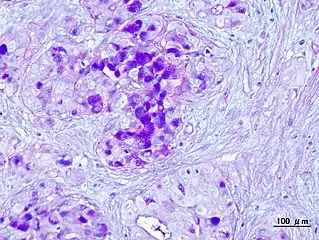

a-d)Immunohistochemistry for CD44 in Mucoepidermoid carcinomas

Histopathologic image of mucoepidermoid carcinoma of the major salivary gland. H & E stain

Histopathologic image of mucoepidermoid carcinoma. Postoperative recurrence of the submandibular tumor. Alcian blue-PAS stain